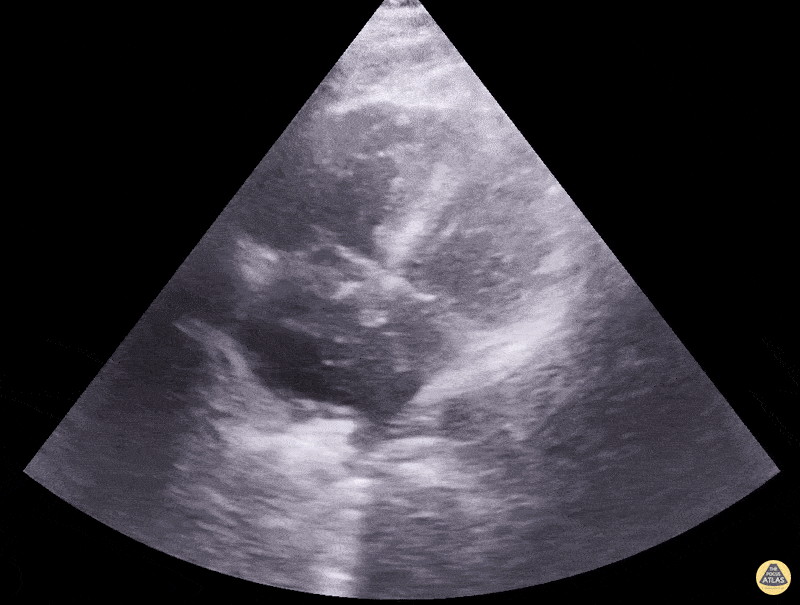

Right Ventricular Dysfunction - McConnell Sign with RV Enlargement

Clip showing McConnell Sign and right side heart enlargement consistent with acute RV strain. While this can be seen in acute pulmonary embolism, it can also be seen in other conditions that cause acute RV dysfunction such as MI or pHTN. Dimitri Livshits DO, Ultrasound Fellow; Jane Belyavskaya MD, Ultrasound Fellow; Chris Hanuscin MD, Ultrasound Division Director (Kings County/SUNY Downstate)